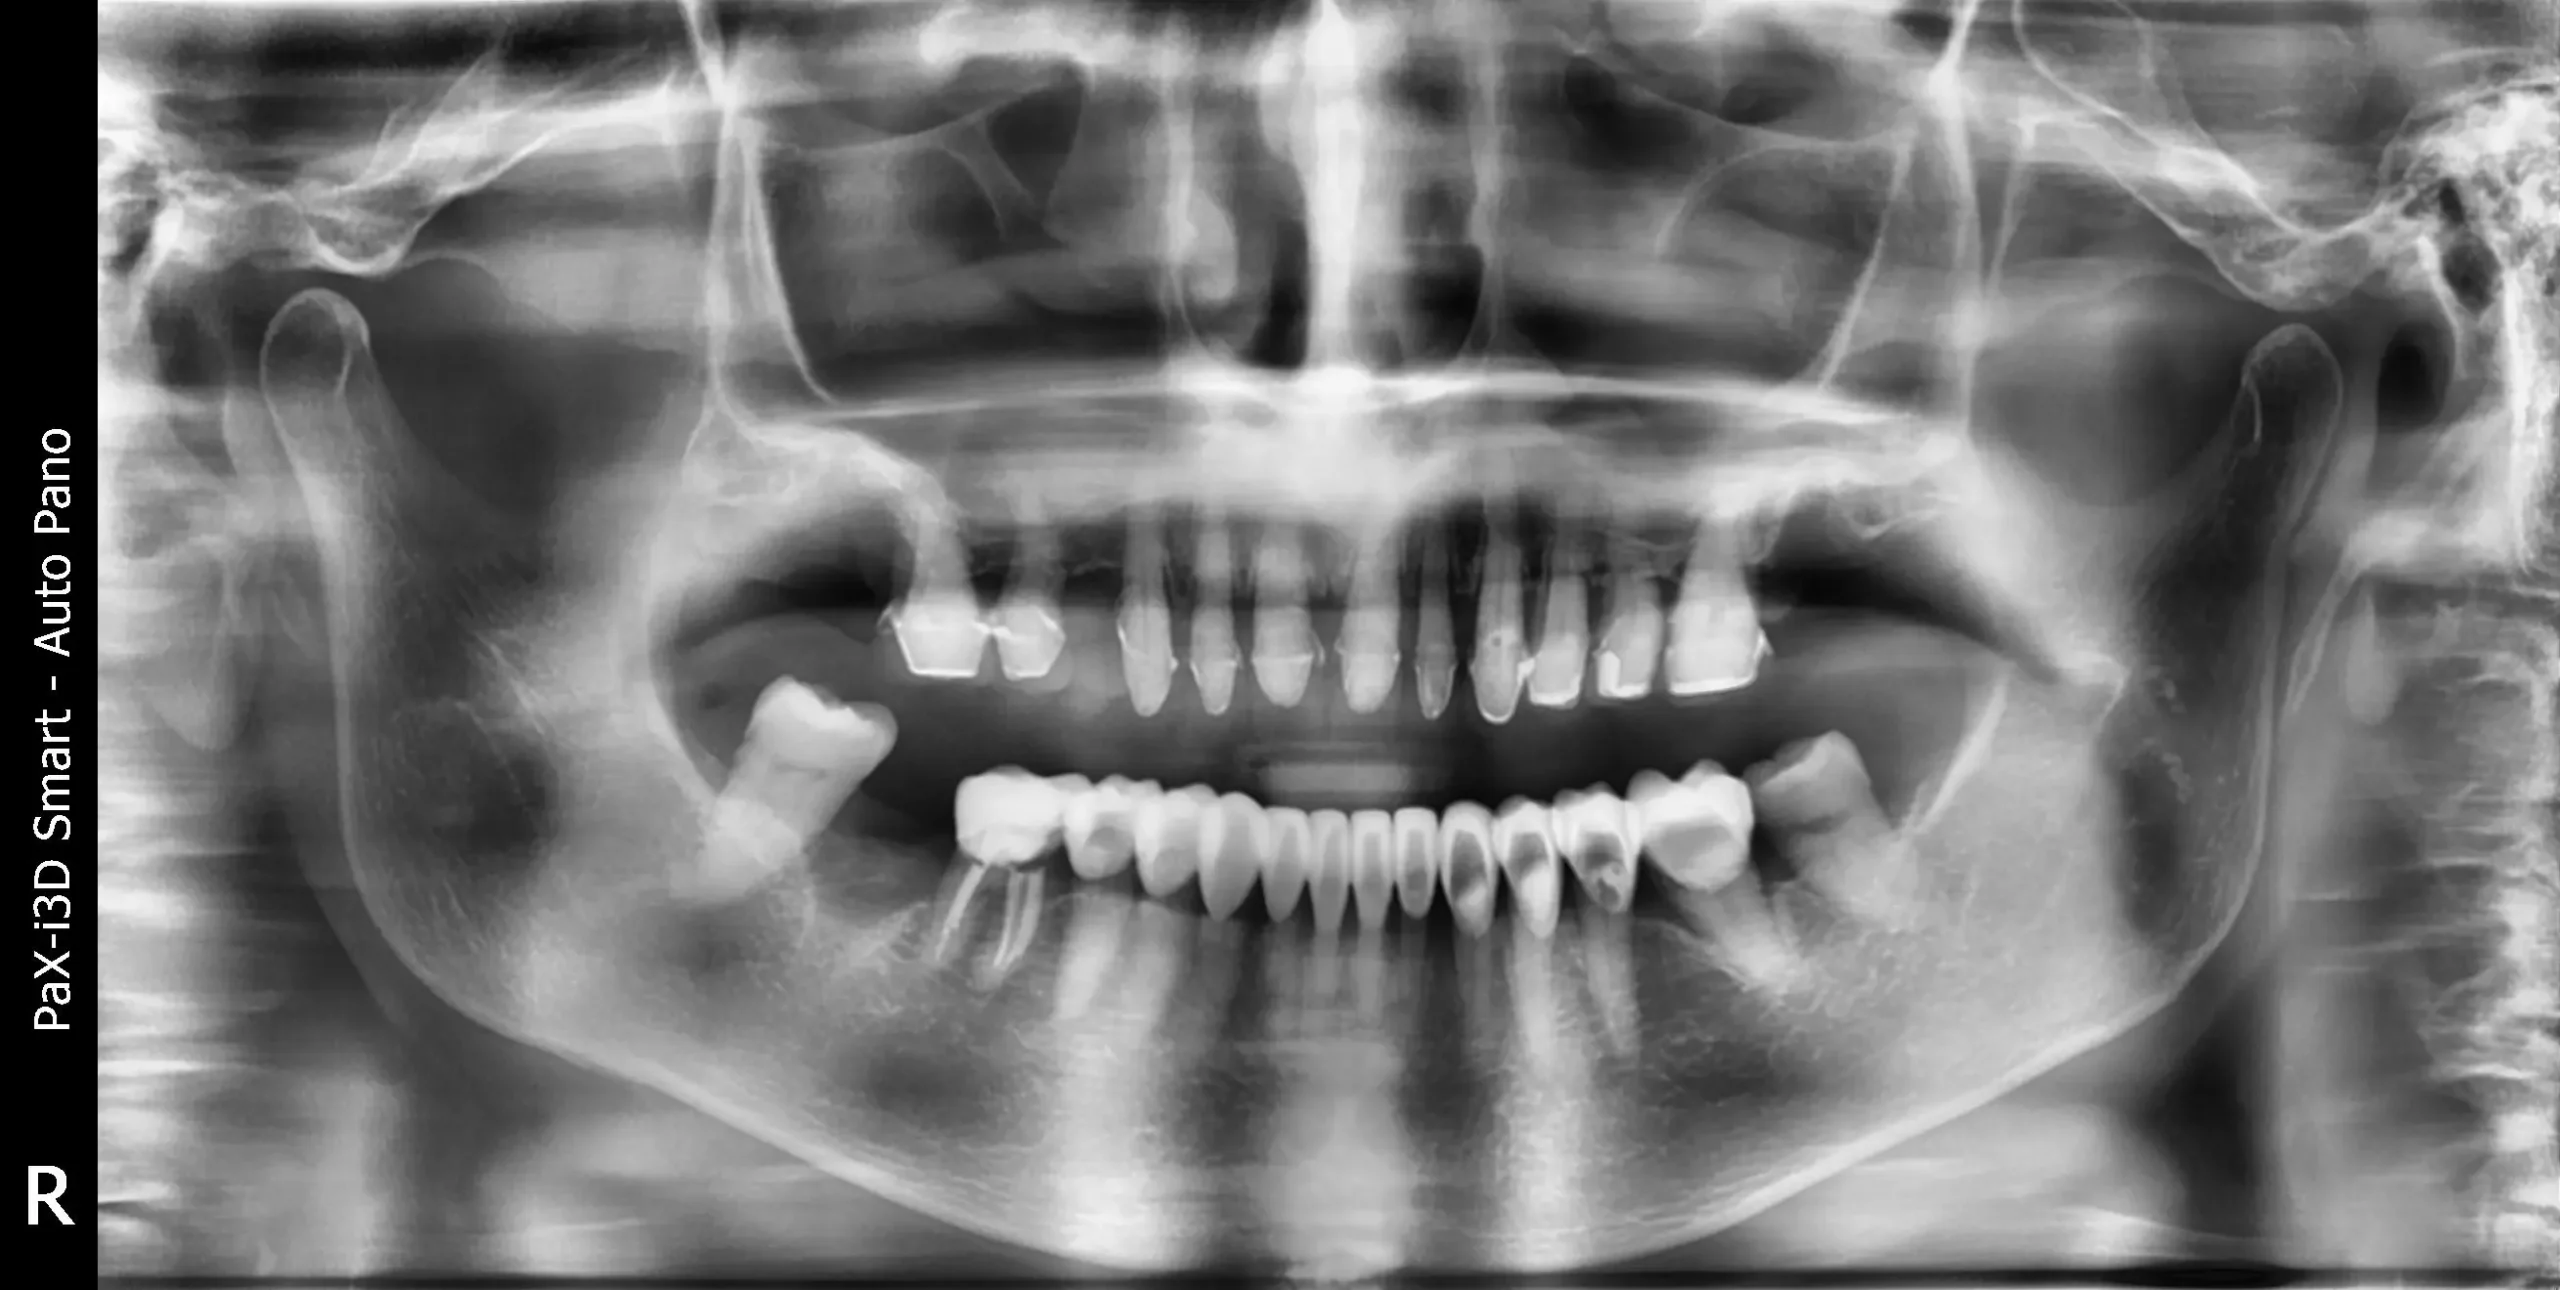

Diagnóstico Diagnóstico

1. Enfermedad periodontal avanzada

2. Pérdida ósea significativa

3. Desgaste del esmalte dental

4. Pérdida de la capacidad masticatoria